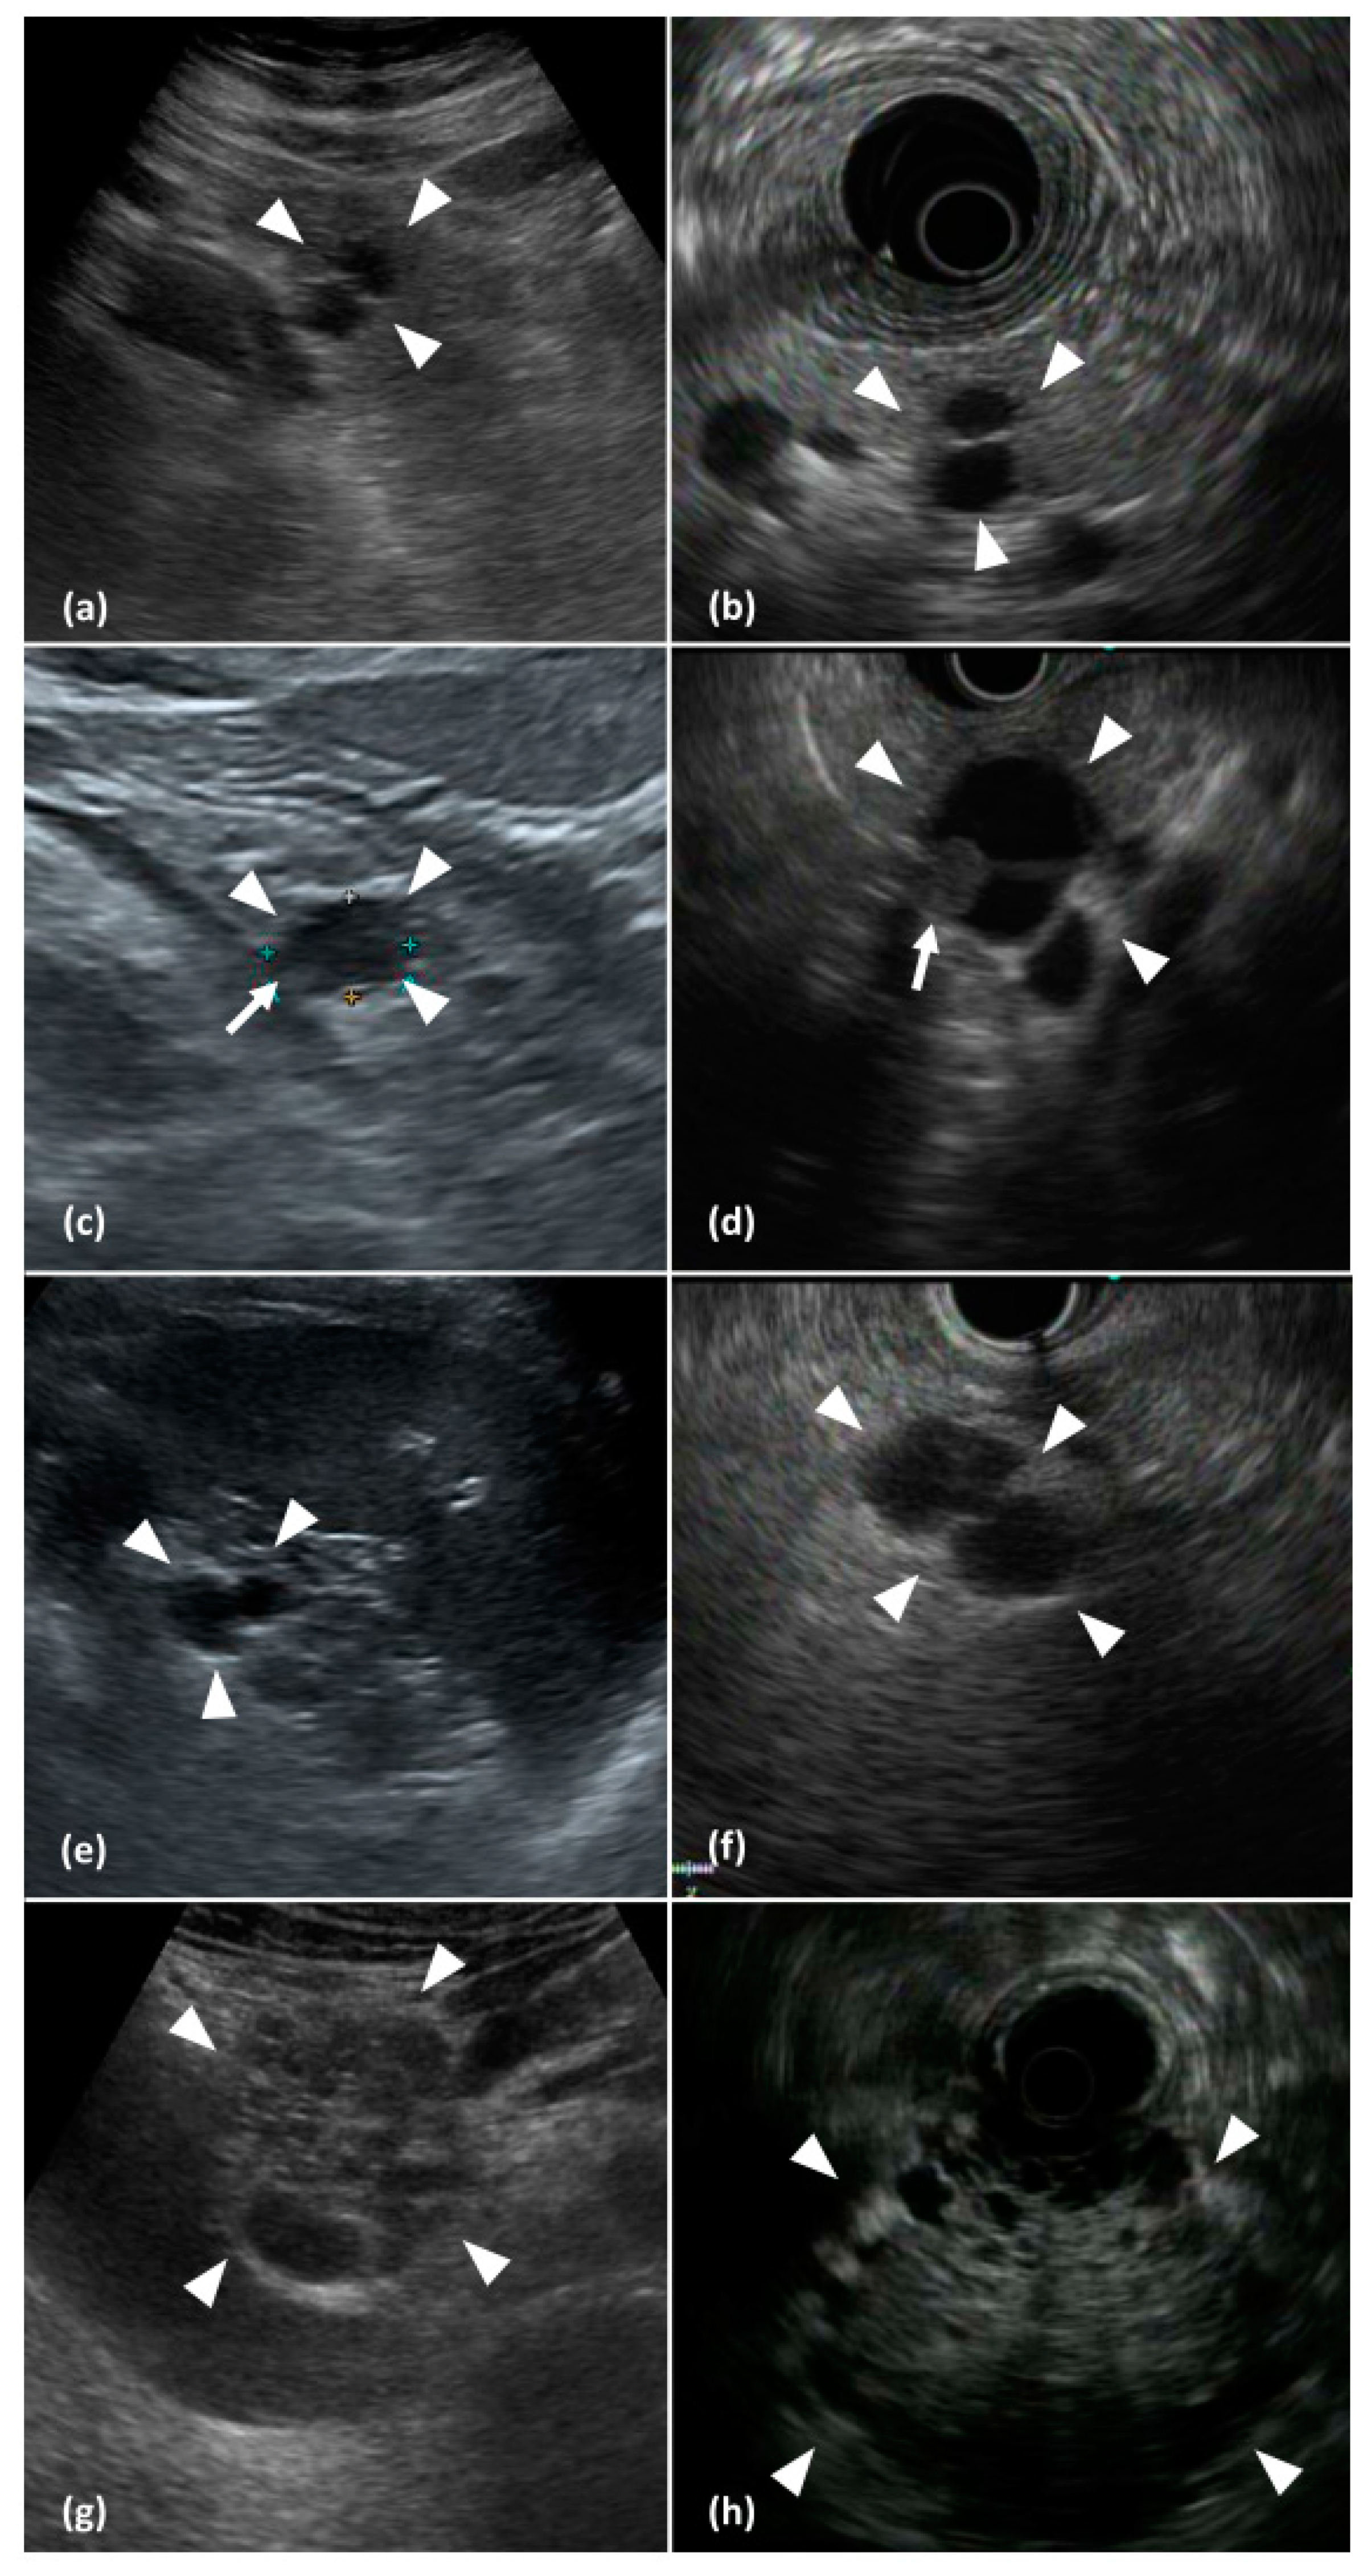

2.2. Image Evaluation